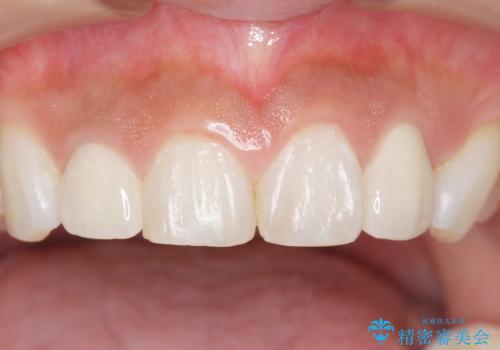

矯正せずに早く治したいという強いご希望により、セラミッククラウンによる補綴治療(上顎両側2の2本)を行いました。

天然歯のような自然な仕上がりに大変喜んで頂けました。

クラウンの種類:オールセラミッククラウン スペシャル